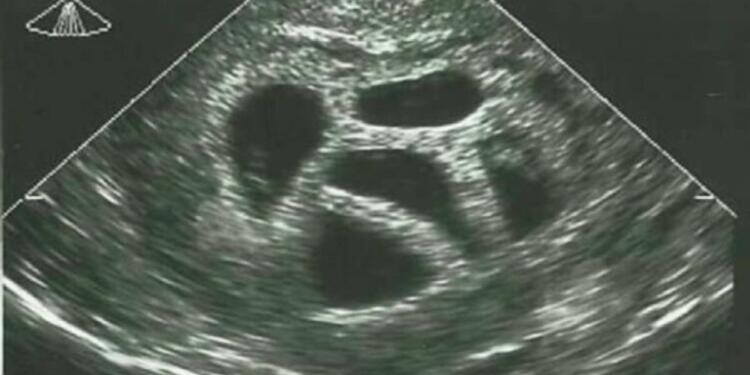

Δεν ήταν έγκυος ούτε σε ένα, ούτε σε δύο αλλά σε πέντε μωρά! Είναι κάτι σπάνιο να συμβεί, αλλά για την Σούζαν έγινε πραγματικότητα. Η 28χρονη τότε μητέρα, συμβουλεύτηκε από τον γιατρό της να ματαιώσει την εγκυμοσύνη, και να κάνει επιλεκτική έκτρωση, αλλά εκείνη αρνήθηκε. Δείτε την φωτογραφία 20 χρόνια μετά!

Αλλά τι είναι μια επιλεκτική έκτρωση; Είναι μια μορφή θεραπευτικής έκτρωσης. Ένα ή περισσότερα έμβρυα αφαιρούνται για να αυξήσουν την πιθανότητα επιβίωσης για τα υπόλοιπα. Η επιλεκτική άμβλωση χωρίς ιατρικούς λόγους που βασίζονται μόνο στο φύλο είναι παράνομη.